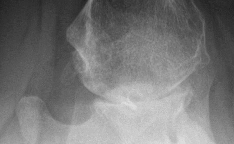

Risk for osteonecrosis associated with this injury is most related to